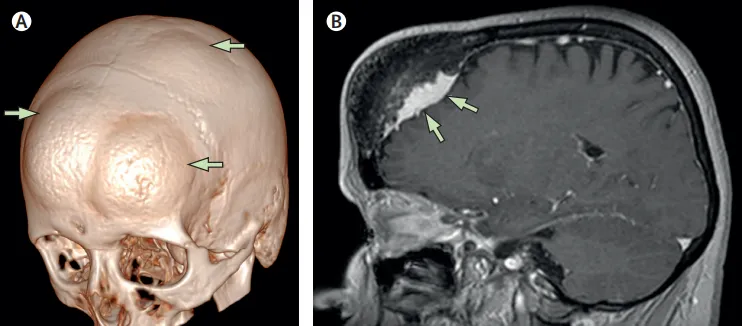

医生,我头上这是怎么了?突然起了3个这么大的包? 最近有没有撞到或者受过其他外伤? 没有啊 那先安排做个脑部核磁共振和CT检查看看。 这是一位58岁的女性患者,2021年5月因发现头顶多处...